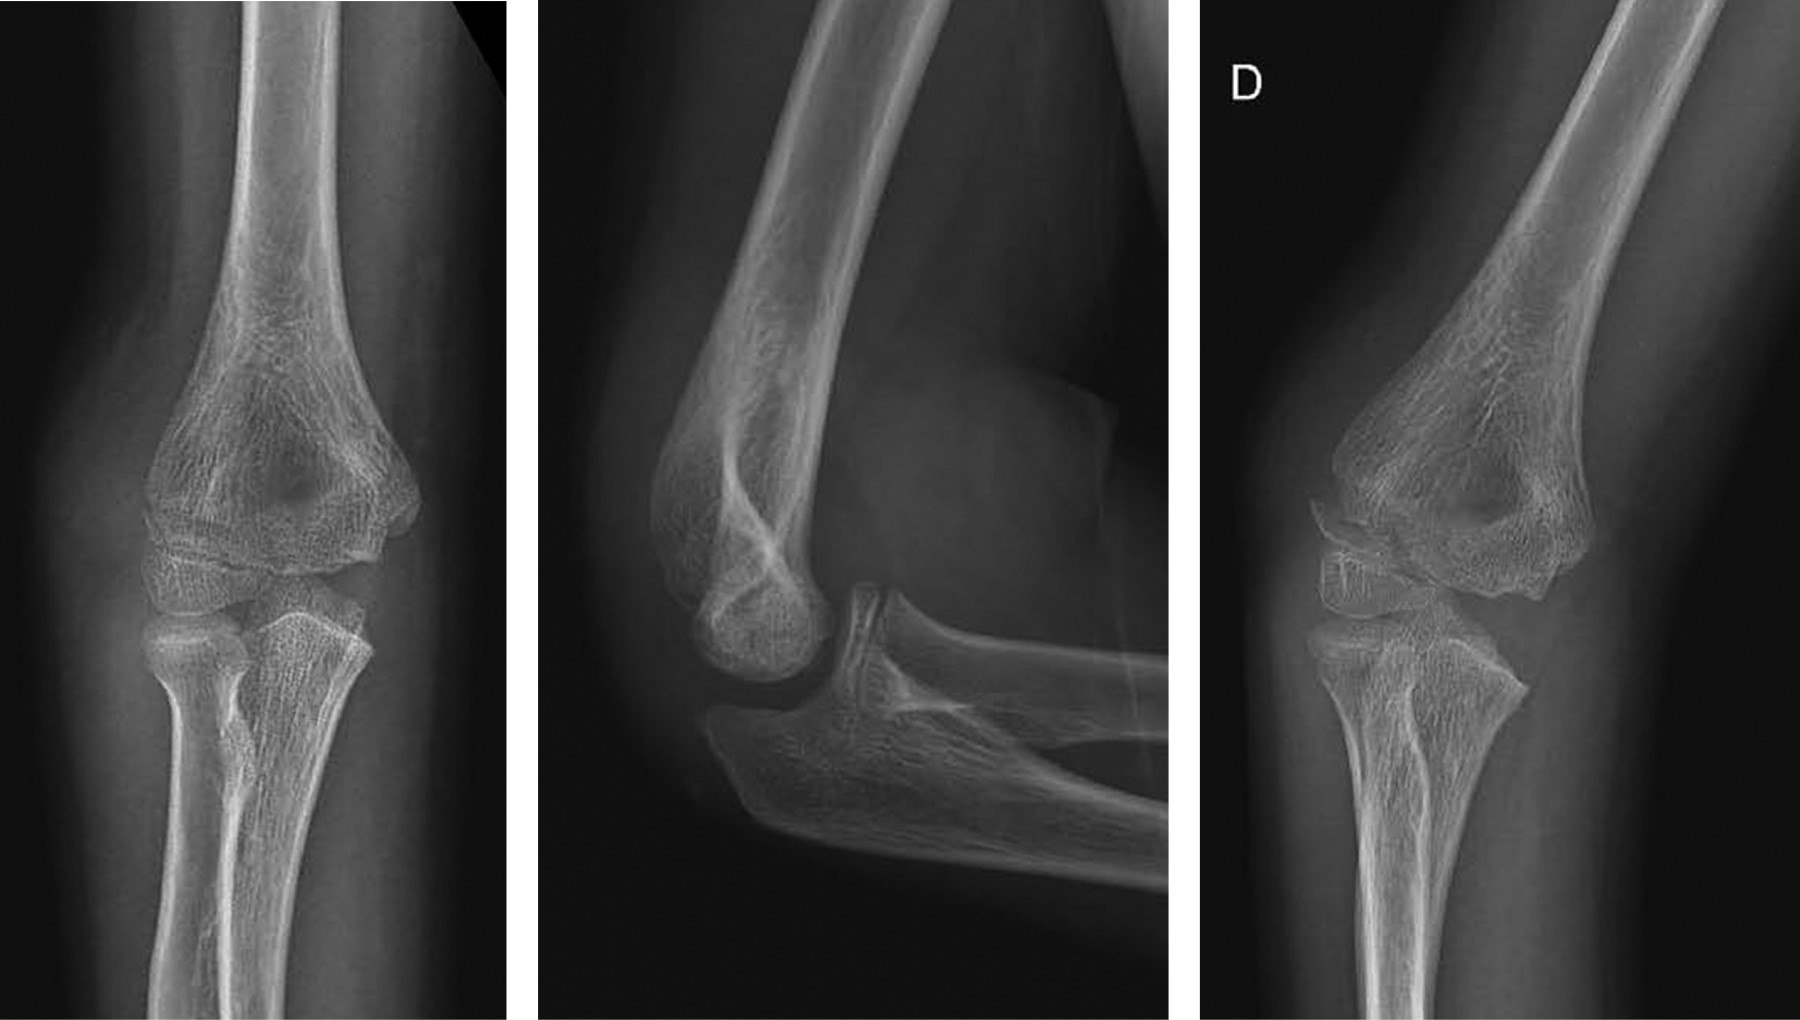

Masculino 14 años – Fractura de epitróclea con 5 mm desplazamiento sin luxación de codo (Figura 2).

• 1. Tratamiento conservador – Dra. Nurhy Rinas (SAOTI):

Las fracturas de epitróclea representan de 12 a 20% del total de todas las lesiones alrededor del codo.30 Existe gran controversia respecto al tratamiento de las fracturas cerradas con y sin asociación de luxación, en ausencia de un fragmento encarcelado. Algunos autores sostienen que la intervención quirúrgica es necesaria en lesiones abiertas, fragmentos encarcelados, sintomatología cubital o inestabilidad asociada de codo.31,32 Otros autores han recomendado la cirugía para fracturas con desplazamiento > 2 mm.33